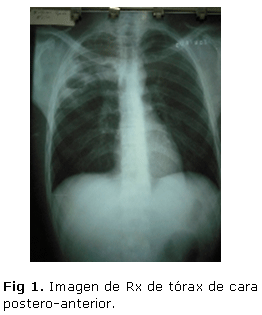

Rx Tórax Postero-anterior (Figura 1) y lateral derecha (Figura 2).

No se definen alteraciones del área cardiaca ni del resto del mediastino.

En LSD se visualizan varias imágenes redondeadas con centro radio- transparente y periferia radiopaca que impresionan corresponder con abscesos en formación, 2 localizados hacia la parte lateral del LSD y uno adyacente al contorno superior derecho del mediastino. No se definen alteraciones del resto del parénquima pulmonar. No se definen otras alteraciones pleurales.

Imágenes radiopacas con niveles hidroaéreos en su interior y áreas radiopacas difusas alrededor de las mismas en relación con abscesos pulmonares en evolución con signos de neumonitis asociada. En la vista lateral, se comprueba que dichas lesiones se encuentran localizadas en el segmento posterior del LSD. TAC de Tórax (Figura 3).